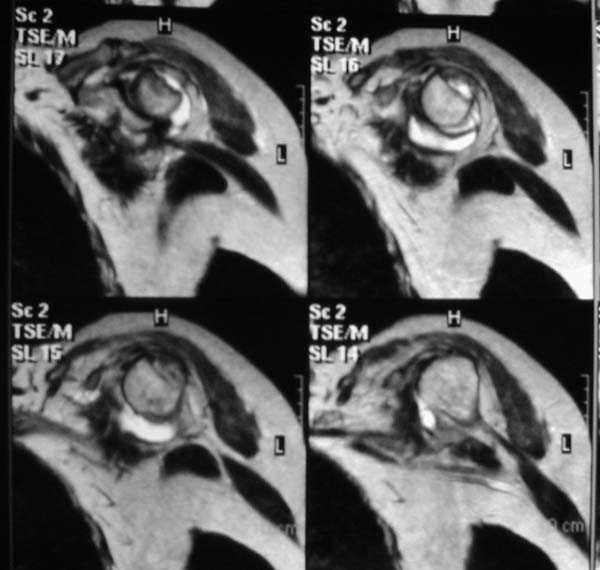

r1r2r3

Уважаемые коллеги!Женщина, 60 лет. 3 недели назад упала с упором на отведенную левую руку. Почувствовала боль в левом плечевом суставе. За помощью не обращалась. 2 недели "мази и припарки". Затем - рентгенограмма (r1 и r2), жалобы на боли,ограничение движений...

Активное отведение 80 гр., при пальпации - головка плечевой кости безболезненно вправляется и тут же самостоятельно вывихивается. Наложена косыночная иммобилизация, рентгенография (r3) и МРТ.В нашем диагностическом центре МРТ исследование плечевого сустава выполнено впервые, опыта у нас маловато :(.Вопросы: уточнение диагноза? какие исследования провести? тактика лечения?

МРТ1МРТ2МРТ3МРТ4

Из того, что видно на недостаточно качественно отсканированных МРТ - нижний подвывих плеча и синовиит. Непонятный очаг по заднему контуру головки плеча (то ли артефакт, то ли косой срез, проходящий между головкой и большим бугорком). Сухожилия вращательной манжетки выглядят целыми. Неправильная форма нижней части labrum glenoidale - разрыв ?

И еще одно пожелание - МРТ костно-суставной системы ОБЯЗАТЕЛЬНО нужно проводить с использованием сканов с подавлением сигнала от жировой ткани (SPIR - на Филипсах, у Вас, как я вижу - Филипс; FATSAT - на других томографах, либо STIR - есть на любых аппаратах). Только так можно увидеть отек мягких тканей и костного мозга на фоне жировой ткани.

Плоскости при сканировании плеча обязательно должно быть 3

1. Ортогональная поперечная (аксиальная)

2. Косая корональная (параллельно длинной оси диафиза)

2. Косая сагиттальная (так же параллельно диафизу плеча)

МРТ должен показать разрыв манжетки, но признаться я не большой эксперт по чтению МРТ сканов, хотя затемнение, отек мягких тканей по задней поверхности плеча видны Обычные рентгенограммы демонстрируют остеолизис в области большого бугорка.

В приложенном файле - МРТ изображение. Более информативно, чем предыдущий вариант? менее? или также?

Все-таки, должен признать, что такие снимки - суррогат. Информативность чуть-чуть лучше, за счет большего размера. С учетом сложных топографо-анатомических соотношений необходимо иметь картину всех срезов, и смотреть их поочередно, иначе не создается целостной картины, а также иметь возможность манипулировать контрастом. Вот если б снимки были в DICOME - тогда от интерпретации было бы не отвертеться -)

А так, могу только сказать следующее

1. На рентгене - нижний подвывих плеча и очаг остеолиза суставного бугорка с четкими контурами (вдавленный перелом на фоне остеопороза ? доброкачественная опухоль? аваскулярный некроз ? (хотя ни разу не слышал об аваскулярном некрозе плеча..)

2.выраженный выпот в полости сустава

3. Сказать о связках и сухожилиях что-то при снимках в таком режиме не берусь.